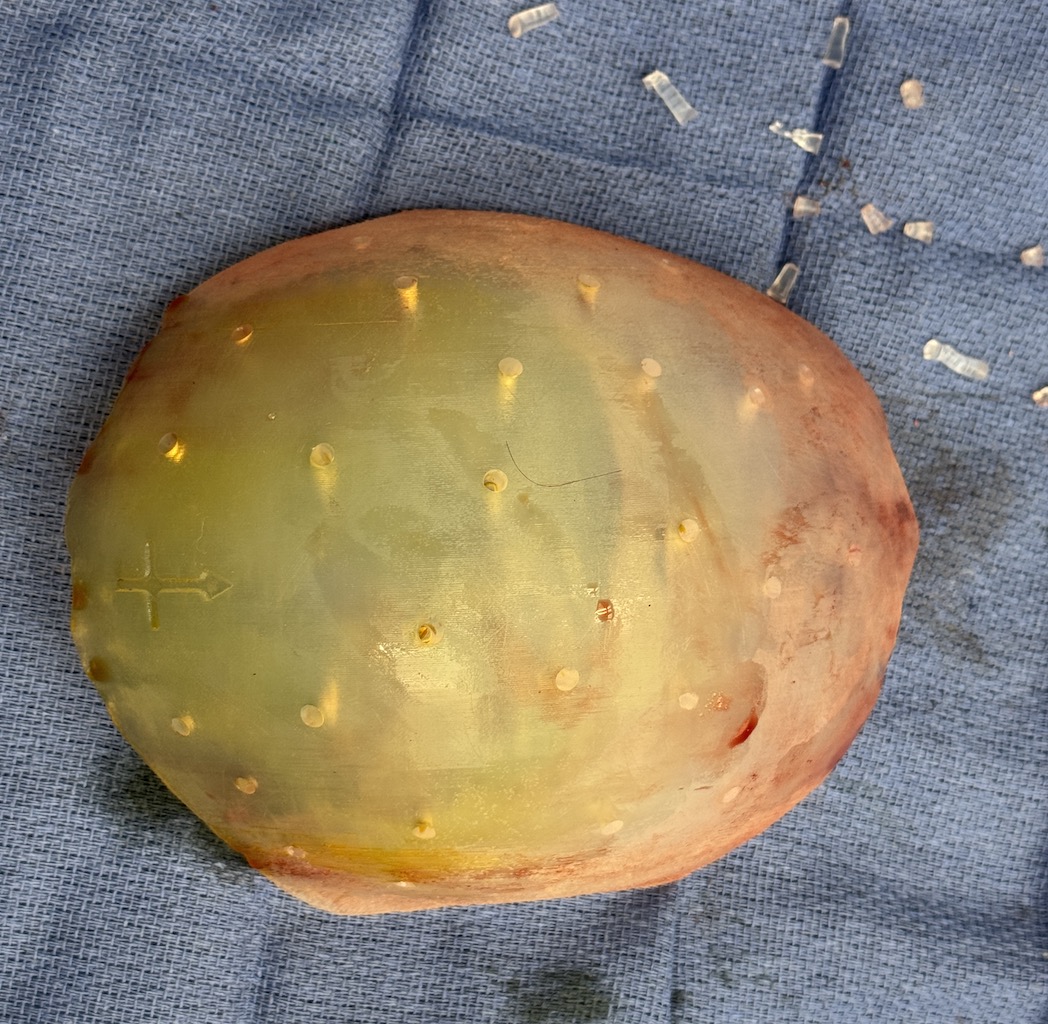

Severe narrowing skull deformity from prior sagittal craniosynostosis repair as an adult.

Complete replacement of entire skull by a custom implant with temporal fat injections.

Severe narrowing skull deformity from prior sagittal craniosynostosis repair as an adult.

Complete replacement of entire skull by a custom implant with temporal fat injections.